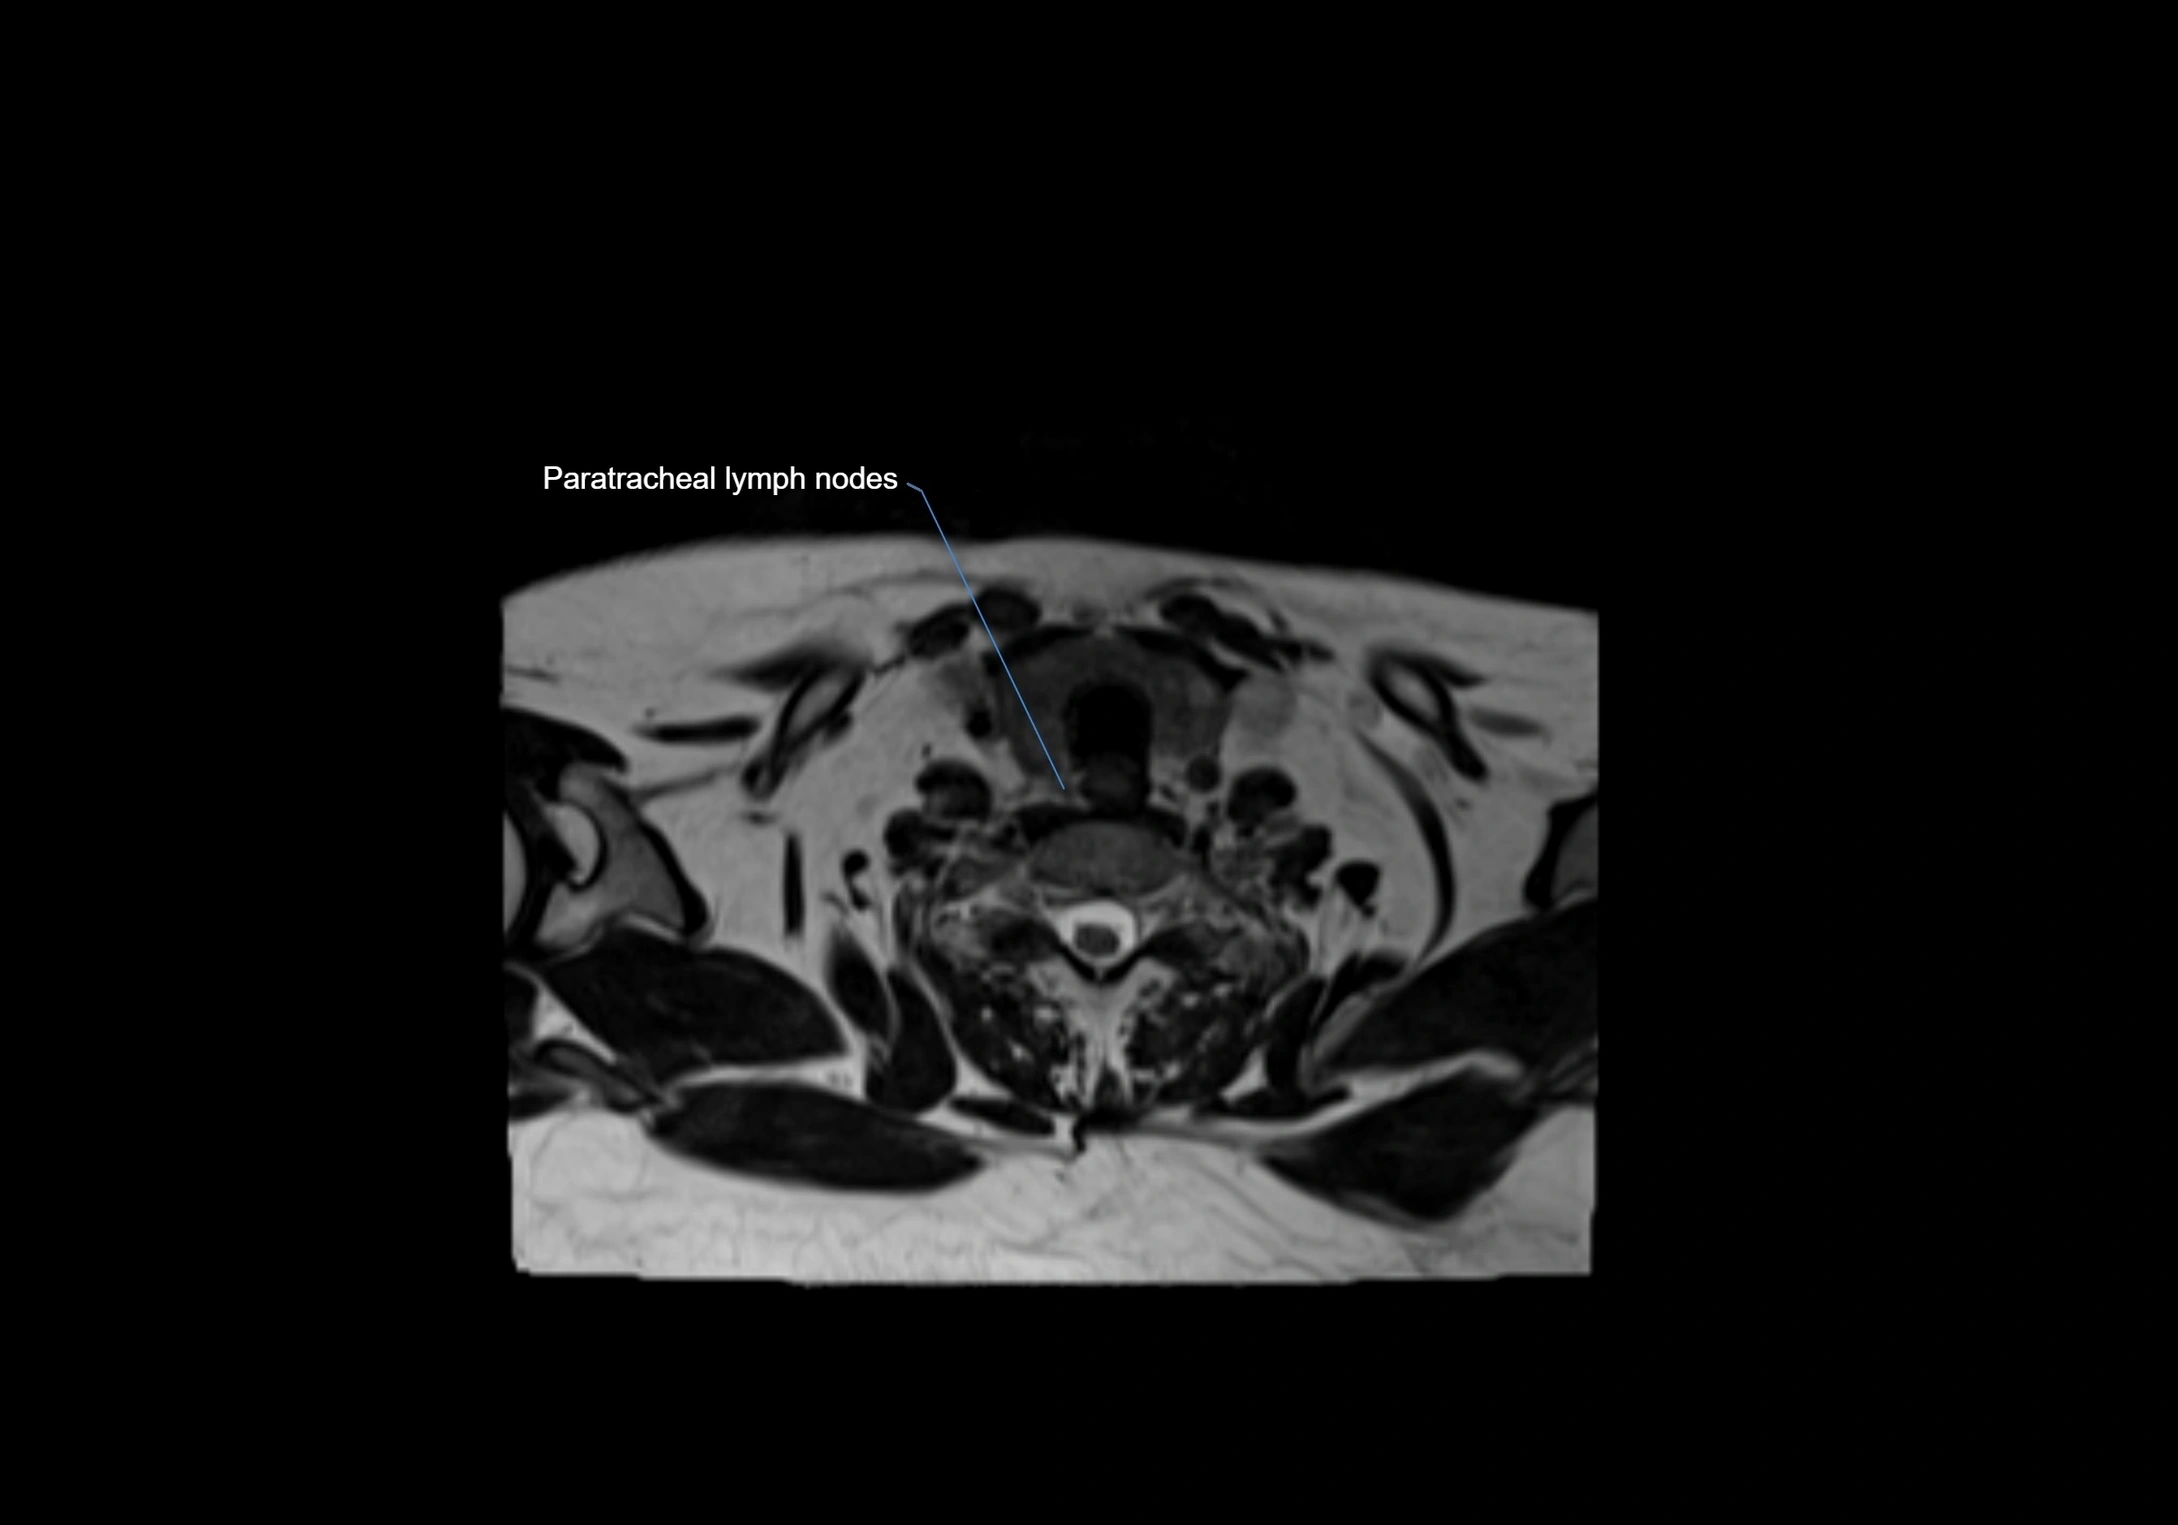

MRI Appearance

T1-weighted images:

• Normal accessory nodes appear as small, oval hypointense to intermediate signal structures within subcutaneous fat

• Surrounded by hyperintense fat, enhancing contrast for visualization

• Pathological nodes may appear enlarged or rounded, sometimes with cortical thickening

T2-weighted images:

• Nodes show intermediate signal, with surrounding fat bright

• Useful for detecting edema, inflammation, or infiltration

• Fatty hilum may appear slightly hyperintense relative to cortex

STIR (Short Tau Inversion Recovery):

• Fat suppression enhances visualization of edematous or pathological nodes

• Normal nodes appear low to intermediate signal, while inflamed or metastatic nodes appear hyperintense

• Useful for detecting subtle lymphadenopathy or early pathology